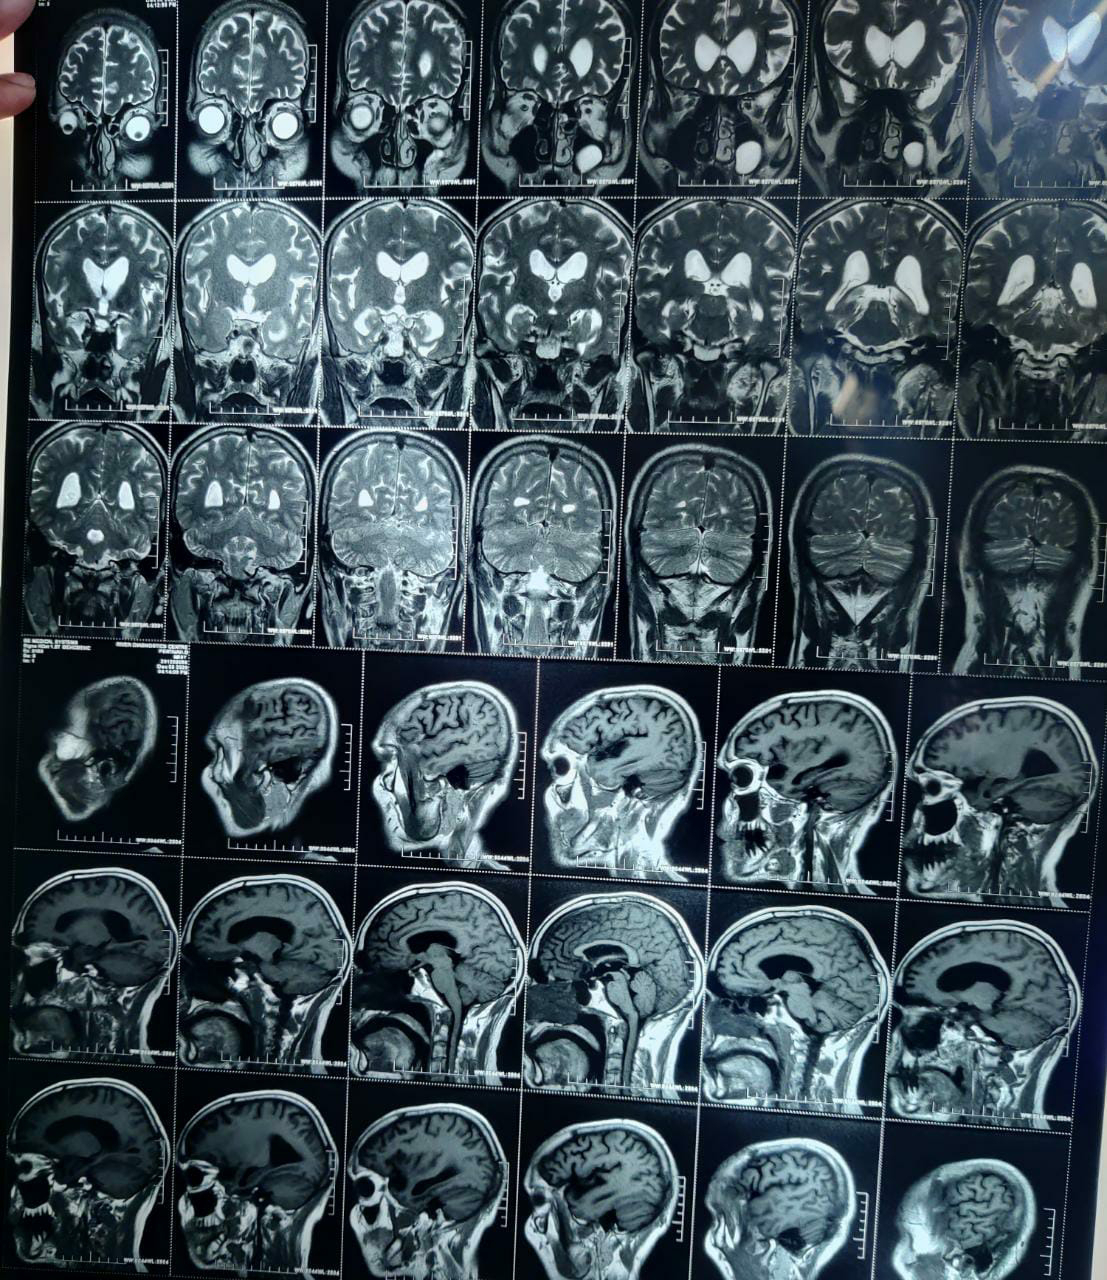

A 58 year old man with unexplanied dementia, slurring of speech and urinary incontinence since 6 months and forgetfulness since 3 months

A 58 year old man,saree maker by occupation was brought to the hospital with h/o

Slurring of speech since 6 months , associated with drooling of saliva from left angle of mouth, food particles and water predominantly from left angle of mouth and smacking of lips

Urinary incontinence since 6 months, dribbling of urine while rushing to bathroom.

Forgetfulness since 3 months, able to remember his name and close relatives. Patient often forgets path to his own home, forgets wearing chappals, patient also wanders sometimes, self hygiene is maintained.

DIAGNOSIS

-Neurodegenerative disease- Alzheimer's disease